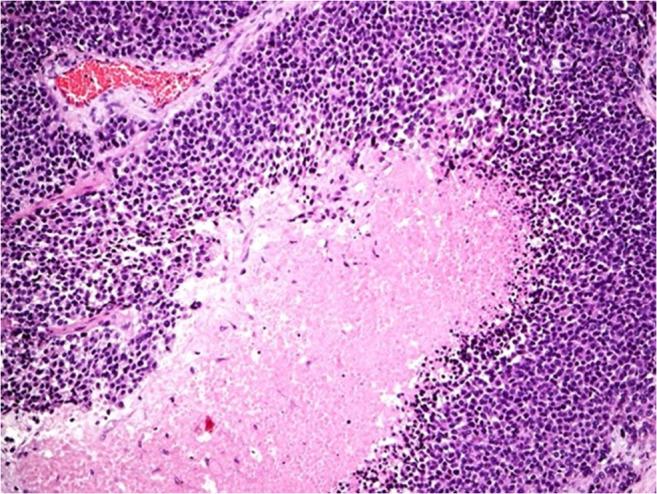

The morphological differentiation between benign and malignant adrenocortical tumors is an ongoing problem in diagnostic pathology. In recent decades the complex scoring systems have been widely used to calculate the probability of malignancy in adrenocortical tumors on the basis of a variety of histomorphological parameters. We herewith present a substantially simplified method to diagnose adrenocortical carcinoma by a single histomorphological parameter on a consecutive series of more than 800 adrenocortical tumors. Between January 2000 and May 2019, altogether 2305 adrenalectomies for of all types of diseases were removed, approximately 98% by minimally invasive approaches. After exclusion of pheochromocytomas, adrenal ganglioneuromas, adrenal metastases, Cushing's disease related specimens, and Conn's adenomas, the present series finally consisted of 837 adrenocortical tumors. All tumors were analyzed by experienced pathologists of a single institution using standard histopathological methods (Hematoxylin-Eosin and Ki67 stained sections). Clinical and histopathologic data were prospectively collected and retrospectively analyzed. Clinically, 385 patients had 420 functioning tumors (FT), and 417 had non-functioning adrenal tumors (NFT). The mean size of FT was 3.8 ± 1.4 cm (range 0.5-16 cm) and for NFT 4.5 ± 1.6 cm (range 1.5-18 cm). Histomorphologically, 32 adrenal tumors were classified as adrenocortical carcinoma (ACC; 3.8%). In all 32 cases (tumor size 9.1 ± 4.0 cm, range 3-18 cm), confluenting tumor necrosis could be demonstrated. The remaining 805 tumors (control group) completely lacked this highly reproducible single morphological feature. Ki67 levels above 10% were found in 31 of 32 ACCs and never in adrenocortical adenomas (ACA). With a mean follow-up of 8.2 years, 24 out of 32 patients primarily diagnosed as ACC developed distant metastases (75.0%), whereas all patients in the control group remained free of local or distant recurrence. We conclude that a single morphological parameter (confluenting tumor necrosis) is sufficient to predict a poor clinical course in adrenocortical tumors. The histomorphological diagnosis of this parameter is straightforward and highly reproducible.

良性与恶性肾上腺皮质肿瘤的形态学鉴别一直是诊断病理学中的难题。近几十年来,复杂的评分系统已被广泛用于根据各种组织形态学参数计算肾上腺皮质肿瘤的恶性概率。在此,我们提出一种大幅简化的方法,通过单一组织形态学参数对连续800多例肾上腺皮质肿瘤进行肾上腺皮质癌的诊断。2000年1月至2019年5月,共进行了2305例各类疾病的肾上腺切除术,约98%通过微创方法进行。排除嗜铬细胞瘤、肾上腺神经节瘤、肾上腺转移瘤、库欣病相关标本和Conn腺瘤后,本系列最终包括837例肾上腺皮质肿瘤。所有肿瘤均由单一机构的经验丰富的病理学家使用标准组织病理学方法(苏木精-伊红染色和Ki67染色切片)进行分析。前瞻性收集临床和组织病理学数据并进行回顾性分析。临床上,385例患者有420例功能性肿瘤(FT),417例有非功能性肾上腺肿瘤(NFT)。FT的平均大小为3.8±1.4 cm(范围0.5 - 16 cm),NFT为4.5±1.6 cm(范围1.5 - 18 cm)。组织形态学上,32例肾上腺肿瘤被分类为肾上腺皮质癌(ACC;3.8%)。在所有32例病例中(肿瘤大小9.1±4.0 cm,范围3 - 18 cm),均可显示融合性肿瘤坏死。其余805例肿瘤(对照组)完全缺乏这种高度可重复的单一形态学特征。32例ACC中有31例Ki67水平高于10%,而肾上腺皮质腺瘤(ACA)中从未发现。平均随访8.2年,最初诊断为ACC的32例患者中有24例发生远处转移(75.0%),而对照组所有患者均无局部或远处复发。我们得出结论,单一形态学参数(融合性肿瘤坏死)足以预测肾上腺皮质肿瘤的不良临床病程。该参数的组织形态学诊断简单且高度可重复。